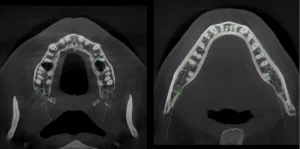

ROCK HILL, S.C., US: 3D Systems has announced the US commercial launch of its NextDent Jetted Denture Solution. The denture system utilises multiple materials in